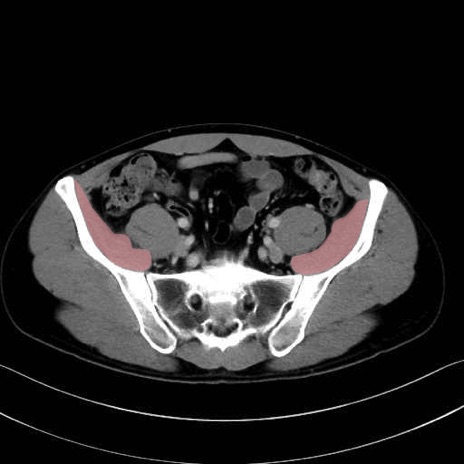

腸骨筋 (Iliacus)